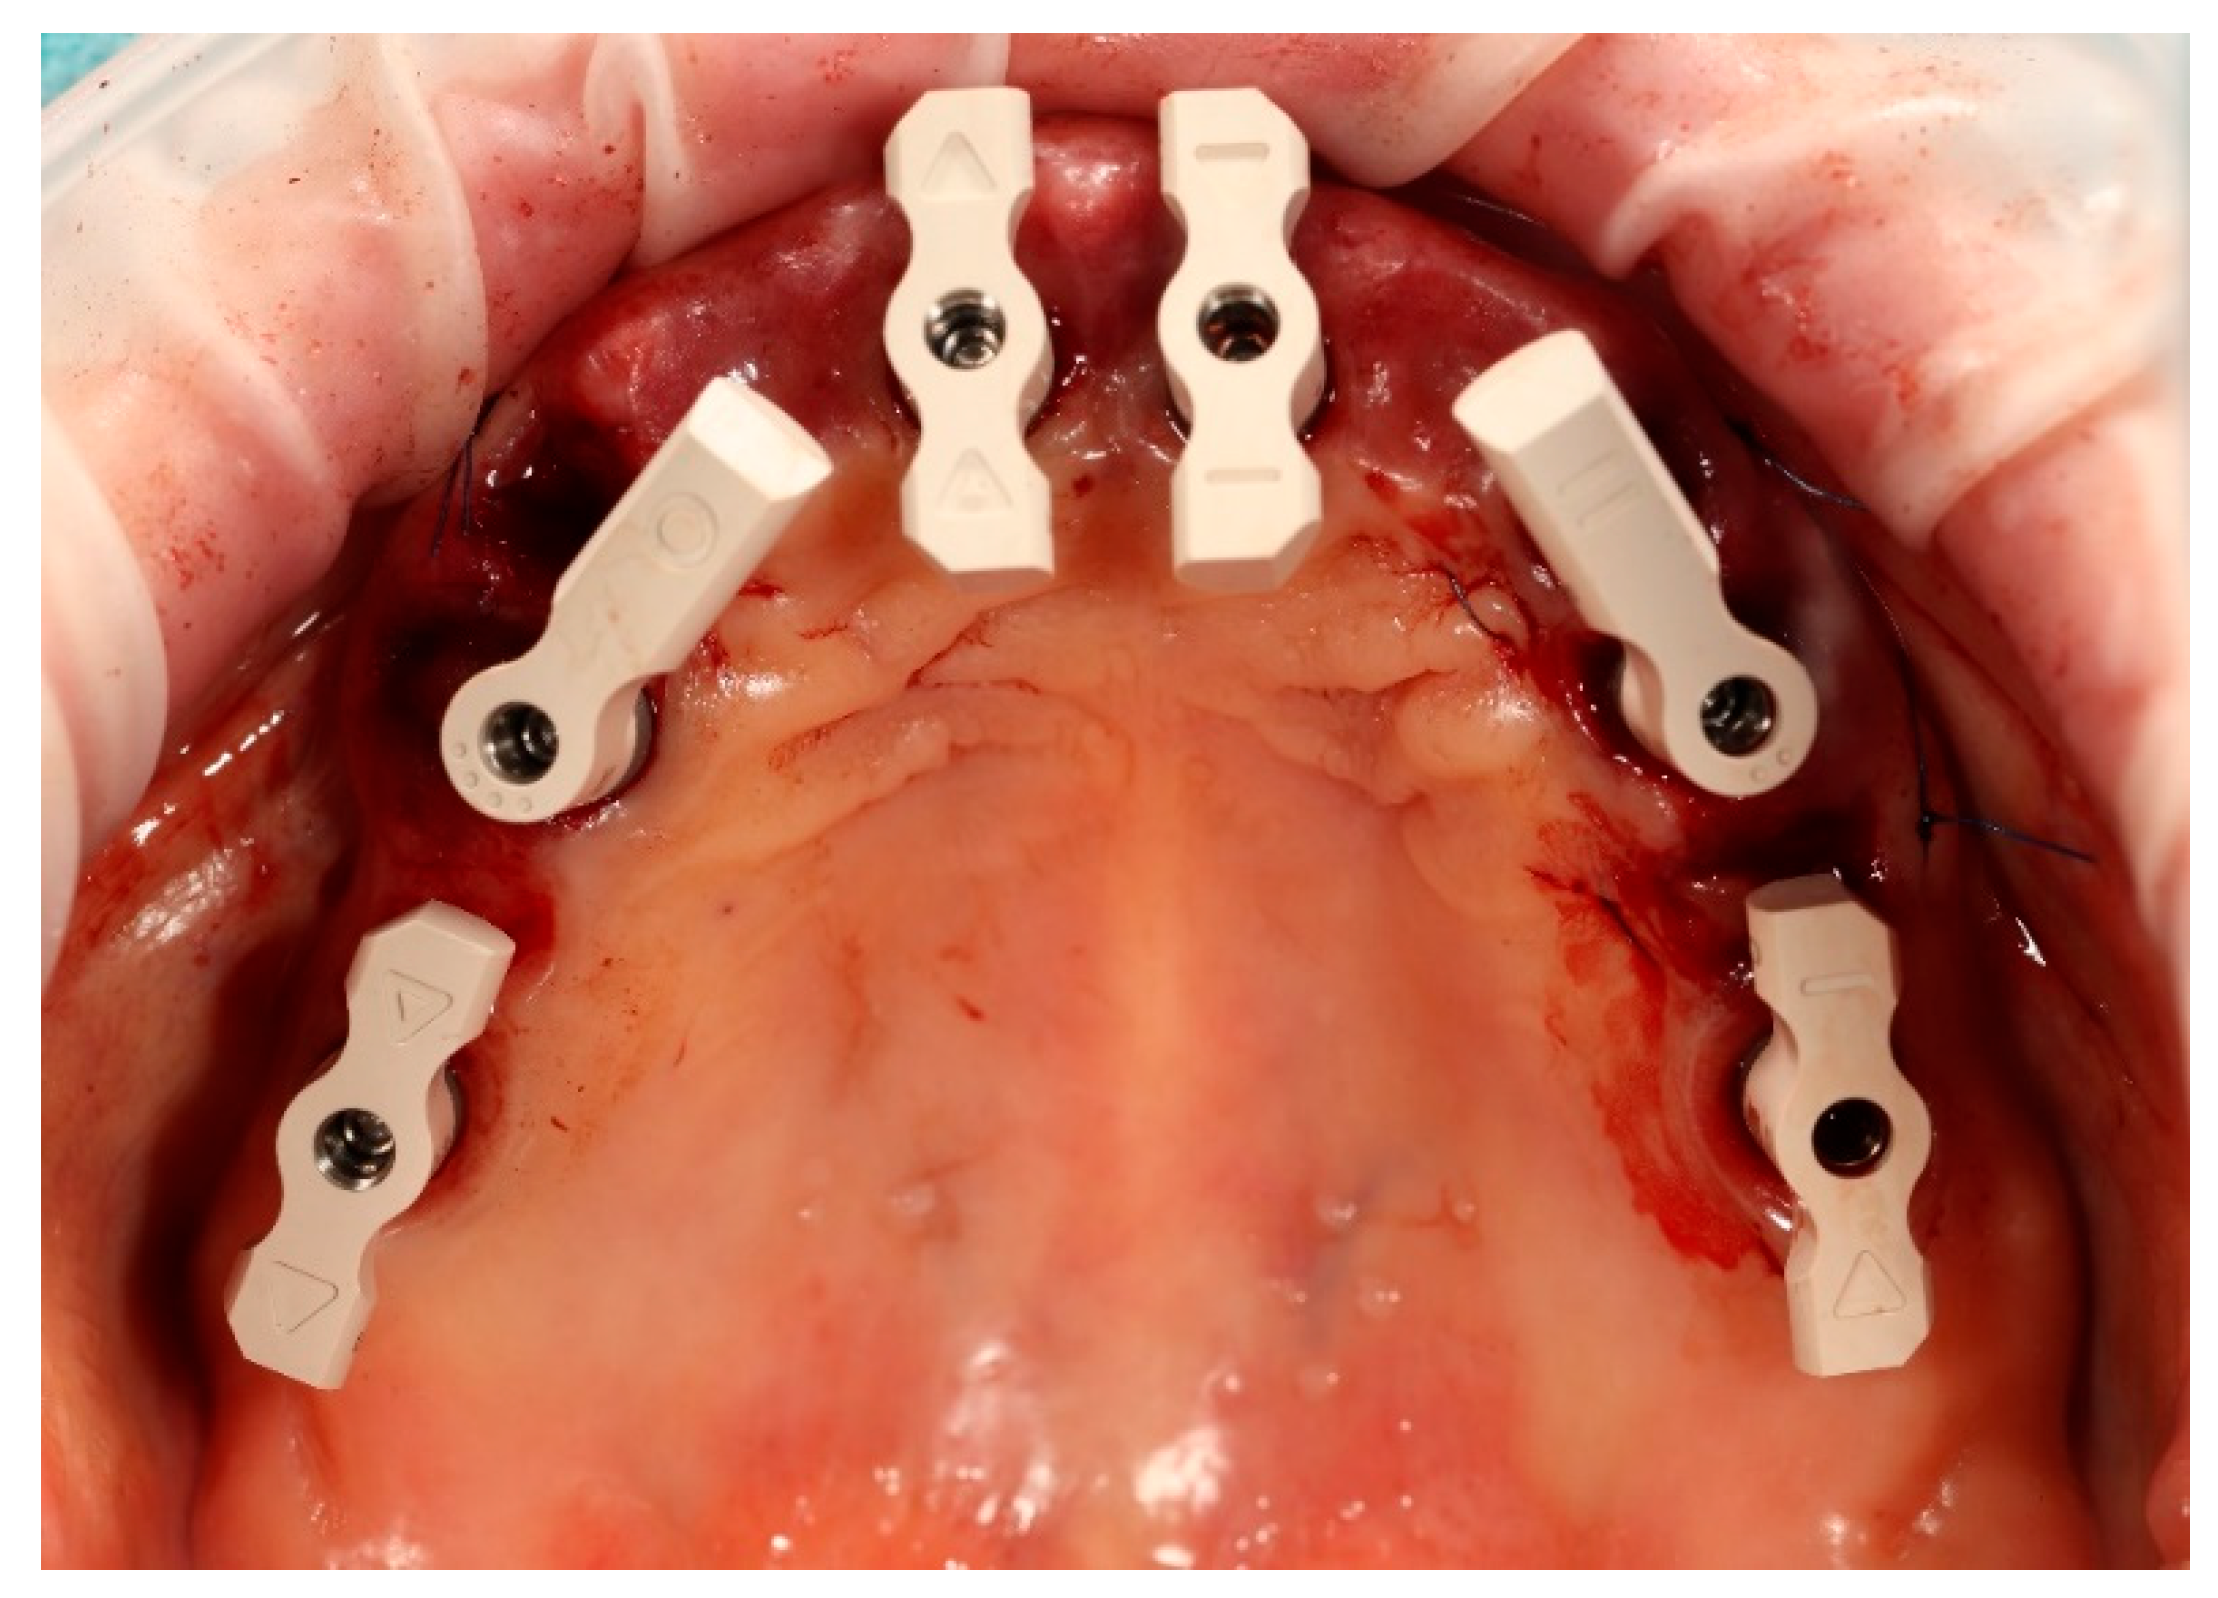

An additional intraoral registration was performed at the level of the multi-unit abutments (MUAs) using scan flags (Shining 3D Tech Co., Ltd., Hangzhou, China) in combination with photogrammetry (Figure 14). This workflow allows the three-dimensional implant positions to be recorded with high trueness and precision, thereby reducing the risk of cumulative errors inherent to conventional intraoral scanner (IOS) stitching, as highlighted in recent in vivo and in vitro studies [2,21].

The Shining3D scan flags are designed to capture IOS and photogrammetry data simultaneously within a controlled and stable scanning pathway. Their integrated fiducial markers enable the software to perform a dual alignment process, cross-referencing implant positions between photogrammetry data, IOS meshes, and the scanned soft tissues. The resulting dataset provides a unified and highly accurate digital model of the clinical situation, which can efficiently be exported to the dental laboratory for prosthetic planning and design [3].

Figure 14. Shining 3D scan flags mounted on the multi-unit abutments in the maxilla prior to the intraoral scanning procedure.